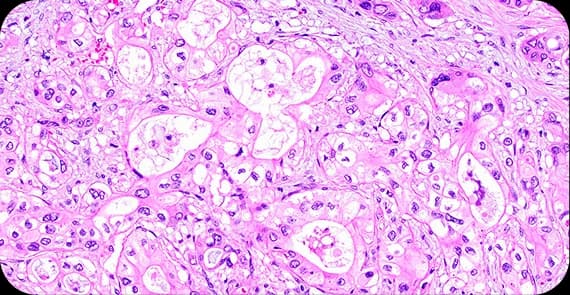

When patients ask what pancreatic cancer is, the explanation begins at the cellular level. Pancreatic cancer occurs when cells in the pancreas develop genetic mutations that cause uncontrolled growth and division.

There are different types of pancreatic cancer depending on the cells from which the tumour arises.

The most common type, originating in the ducts that carry digestive enzymes.

Arise from hormone-producing cells and may behave differently from adenocarcinomas.

Include cystic tumours and acinar cell carcinomas.